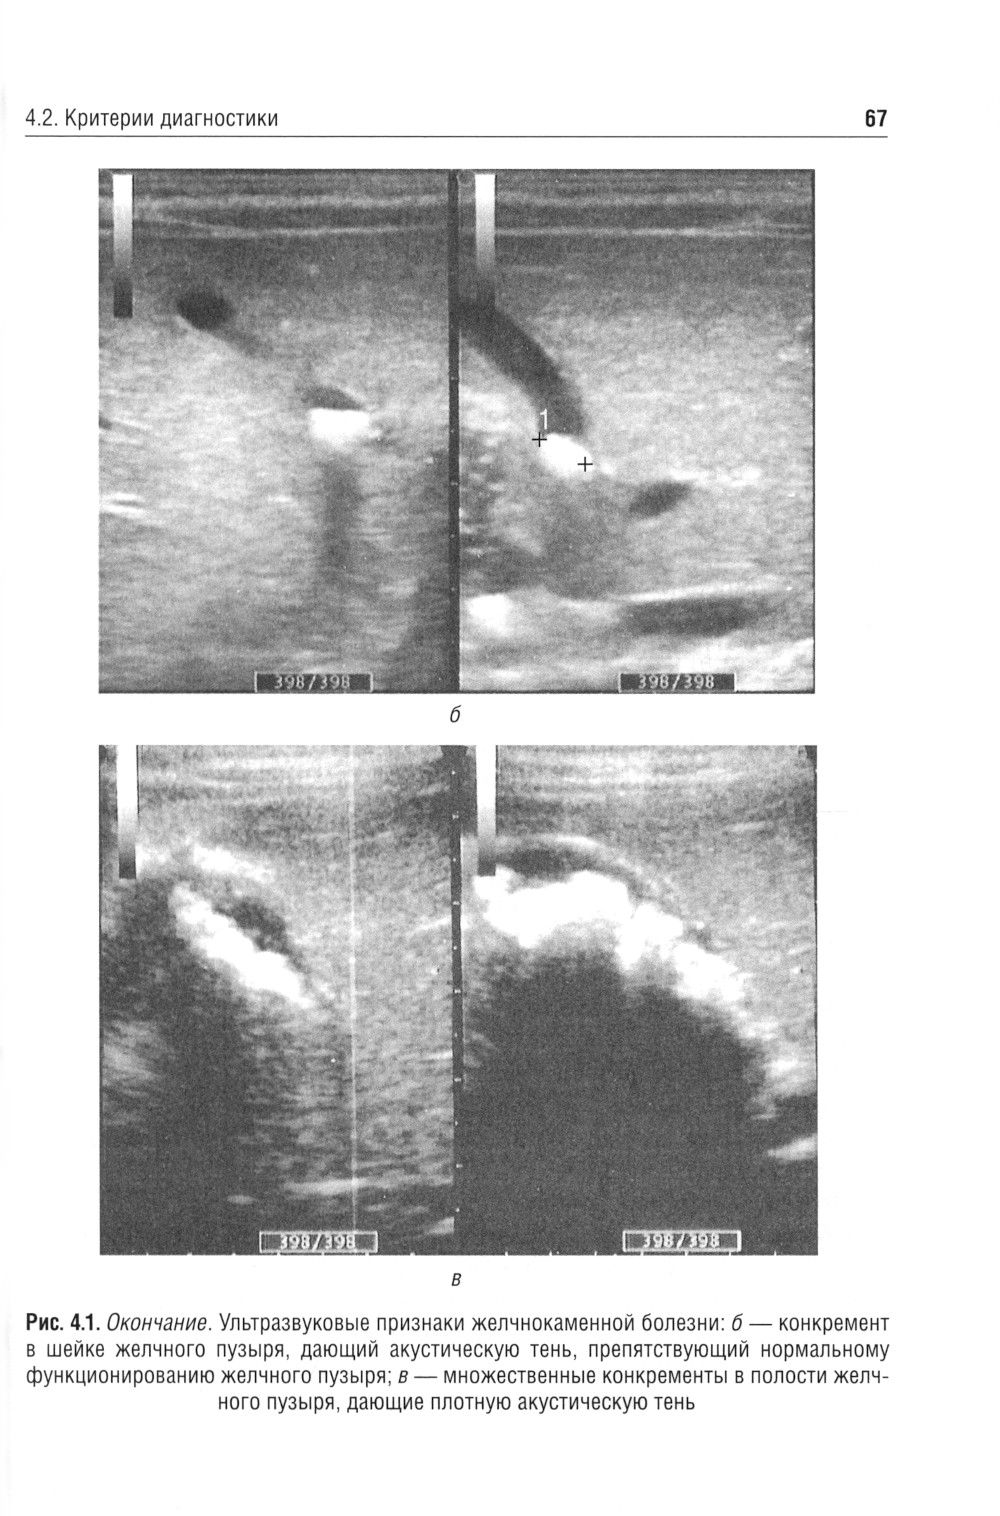

В учебном пособии рассмотрены отдельные морфофункциональные особенности билиарного тракта, вопросы физиологии желчеобразования и желчеотделения, а также представлены материалы, касающиеся диагностики и лечебной тактики дискинезий желчевыводящих путей, хронического холецистита и желчнокаменной болезни. Приведены анамнестические, клинические и дополнительные критерии диагностики, позволяющие оптимизировать диагностическую тактику, а также программы назначения лечебно-коррекционных мероприятий с учетом индивидуальных и возрастных особенностей пациента. Отражены сведения, касающиеся новых клинических вариантов течения билиарных дисфункций у детей, - диспластикоассоциированных дискинезий желчевыводящих путей. Пособие предназначено студентам медицинских вузов, а также врачам-педиатрам, гастроэнтерологам, терапевтам, врачам общей практики.| Издательство | ГЭОТАР-Медиа |